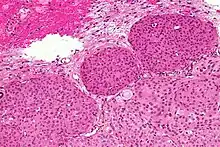

Histopathology of a typical WHO grade 1 meningioma, H&E stain. It is of the meningothelial histologic type, which is the most common meningioma type. It shows its typical findings:

- A woven architectural pattern

- Psammoma bodies (spheroid calcifications)

- Syncytial cells (having indistinct cell membranes) with eosinophilic (pink) cytoplasms

- Round uniform nuclei

- Whorls (concentric cell arrangements)[15]

Histologically, meningioma cells are relatively uniform, with a tendency to encircle one another, forming whorls and psammoma bodies (laminated calcific concretions).[18] As such, they also have a tendency to calcify and are highly vascularized.